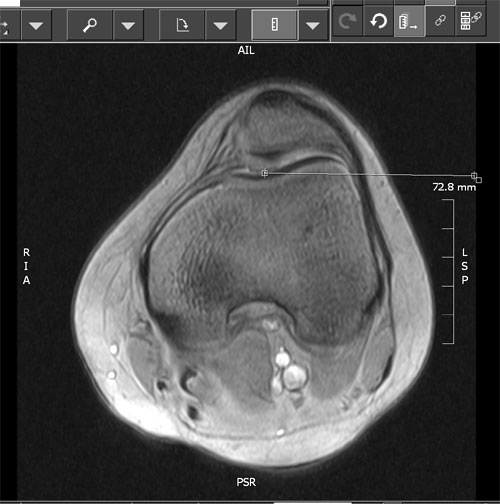

Måling af TTTG afstand (TTTG=Tuberositas Tibia Trochlea

Grove) er en mere præcis måling af Q-vinkel og malalignment:

Brug MR sagitale snit, kør ned til tuberositas og mål afstand fra midten af

tuberositas til kanten af billedet på skærmen. Gentag målingen fra midten af

troclea og træk de to tal fra hinanden. (Målet i eksemplet er 15,3 mm)